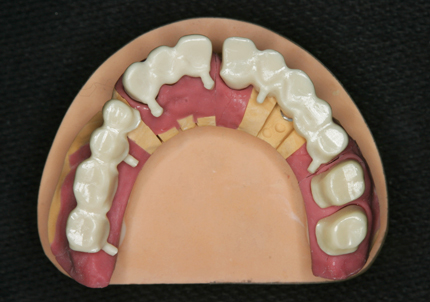

9.セラミック焼成

10.上顎補綴物装着(2008年12月)

12.上顎補綴物装着(2009年5月)